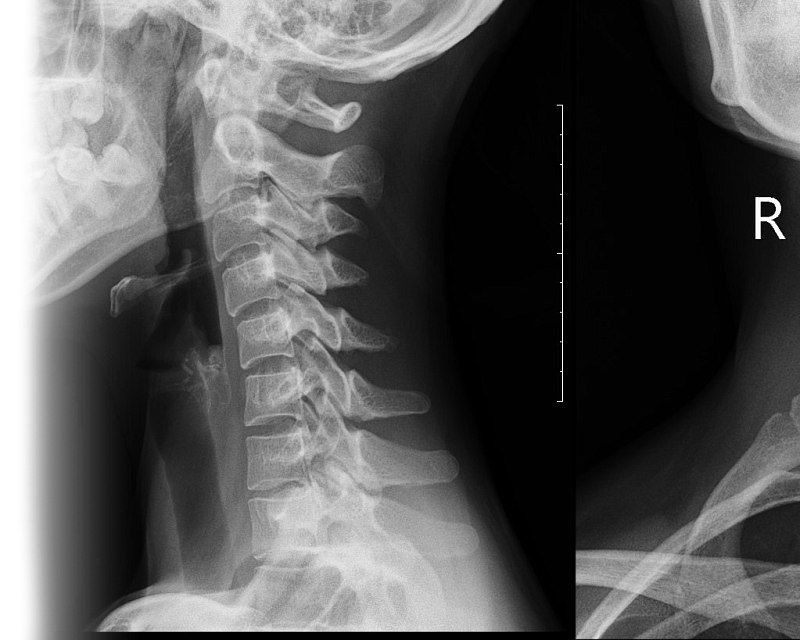

Рентгенография шейного отдела позвоночника Рентгенография шейного отдела позвоночника

Рентгенография шейного отдела позвоночника

Рентгенография шейного отдела позвоночника – важный метод исследования шейного отдела позвоночника для оценки состояния статики позвоночника, структур.

1. Рентгенография шейного отдела позвоночника в 2-х проекциях